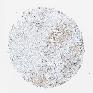

PANCREATIC CANCER - Protein expressioni

A mouse-over function shows sample information and annotation data. Click on an image to view it in a full screen mode. Samples can be filtered based on level of antibody staining by selecting one or several of the following categories: high, medium, low and not detected. The assay and annotation is described here.

Note that samples used for immunohistochemistry by the Human Protein Atlas do not correspond to samples in the TCGA dataset.

Antibody stainingi

Antibody staining in the annotated cell types in the current human tissue is reported as not detected, low, medium, or high, based on conventional immunohistochemistry profiling in selected tissues. This score is based on the combination of the staining intensity and fraction of stained cells.

Each image is clickable and will lead to virtual microscopy that enables deeper exploration of all samples and also displays staining intensity scores, fraction scores and subcellular localization as well as patient and tissue information for each sample.

Antibody HPA013994

Antibody HPA013995

Staining

High

Medium

Low

Not detected

Intensity

Strong

Moderate

Weak

Negative

Quantity

>75%

75%-25%

<25%

None

Location

Nuclear

Cytoplasmic/membranous

Cytoplasmic/membranous,nuclear

Adenocarcinoma, NOS